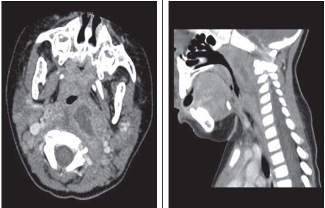

Soft tissue radiograph and CT scans of the neck are shown.

Figure 2 – A CT scan of the neck of the 4-year-old patient shows a retropharyngeal abscess.

Imaging studies. In patients with no signs of airway compromise and in whom the suspicion for retropharyngeal abscess is low, a lateral neck radiograph may be the initial study. When the suspicion is high, a CT scan with contrast is the preferred study.

When retropharyngeal infection (cellulitis or abscess) is present, the depth of the prevertebral space is increased (Figure 1) compared with the anteroposterior measurement of the adjacent vertebral body. Alternatively, the retropharyngeal space is considered pathologically widened when it is greater than 7 mm at C2 or 14 mm at C6 in children, and greater than 22 mm at C6 in adults.4 In some cases, a radiopaque foreign body, soft tissue mass, air-fluid level, or gas is visualized in the prevertebral area. A lateral view obtained during inspiration, with the neck held in normal extension, helps avoid false widening of the retropharyngeal space. False widening of the retropharyngeal space also may be caused by crying, particularly in infants.

CT of the neck with intravenous contrast provides ideal delineation of the retropharyngeal area. A CT scan may show an abscess (Figure 2), with extension to contiguous spaces in the neck or chest, and can differentiate between retropharyngeal abscess and cellulitis. It can also show loculations and the position of the carotid artery and internal jugular vein in relation to the infectious process, which helps guide the surgical approach in patients who require drainage.